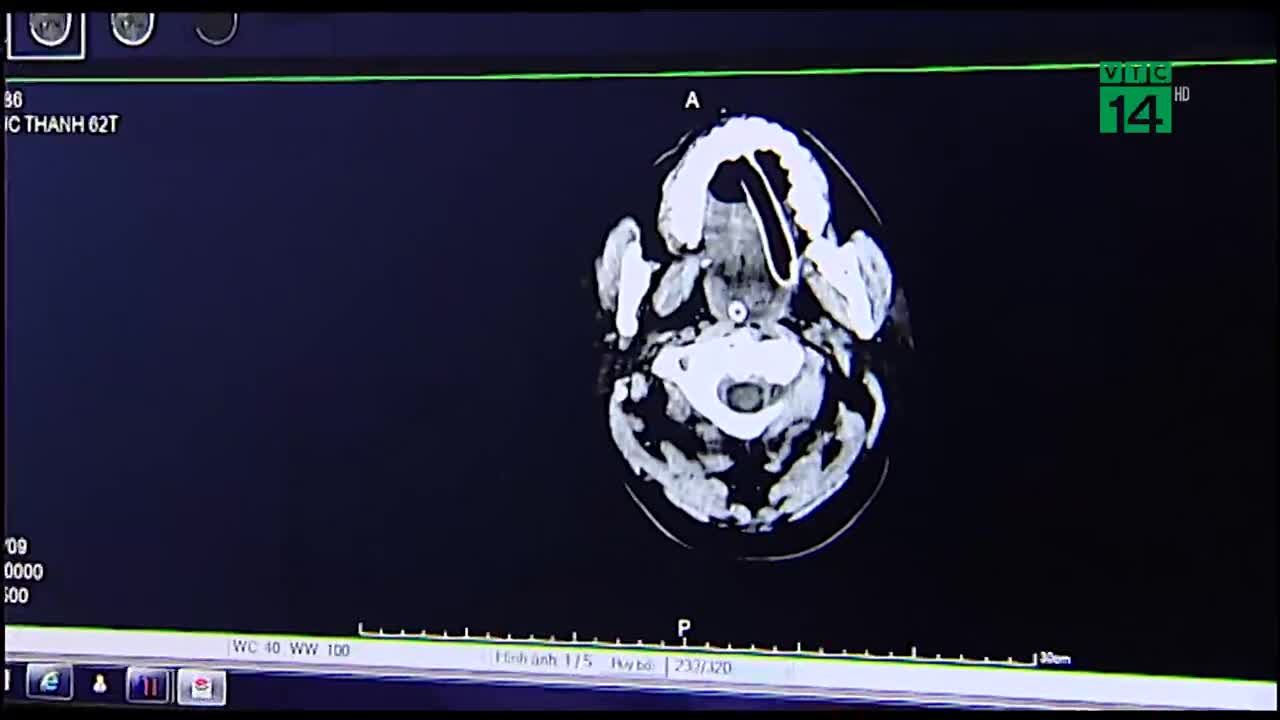

Không chỉ giảm thiểu chi phí khám chữa bệnh, việc số hóa các xét nghiệm, bệnh án còn giúp loại bỏ tối đa những nhầm lẫn và sai sót y khoa.

Ghi nhận tại Quảng Ninh - địa phương đầu tiên ở miền Bắc thực hiện đề án xây dựng bệnh viện thông minh.